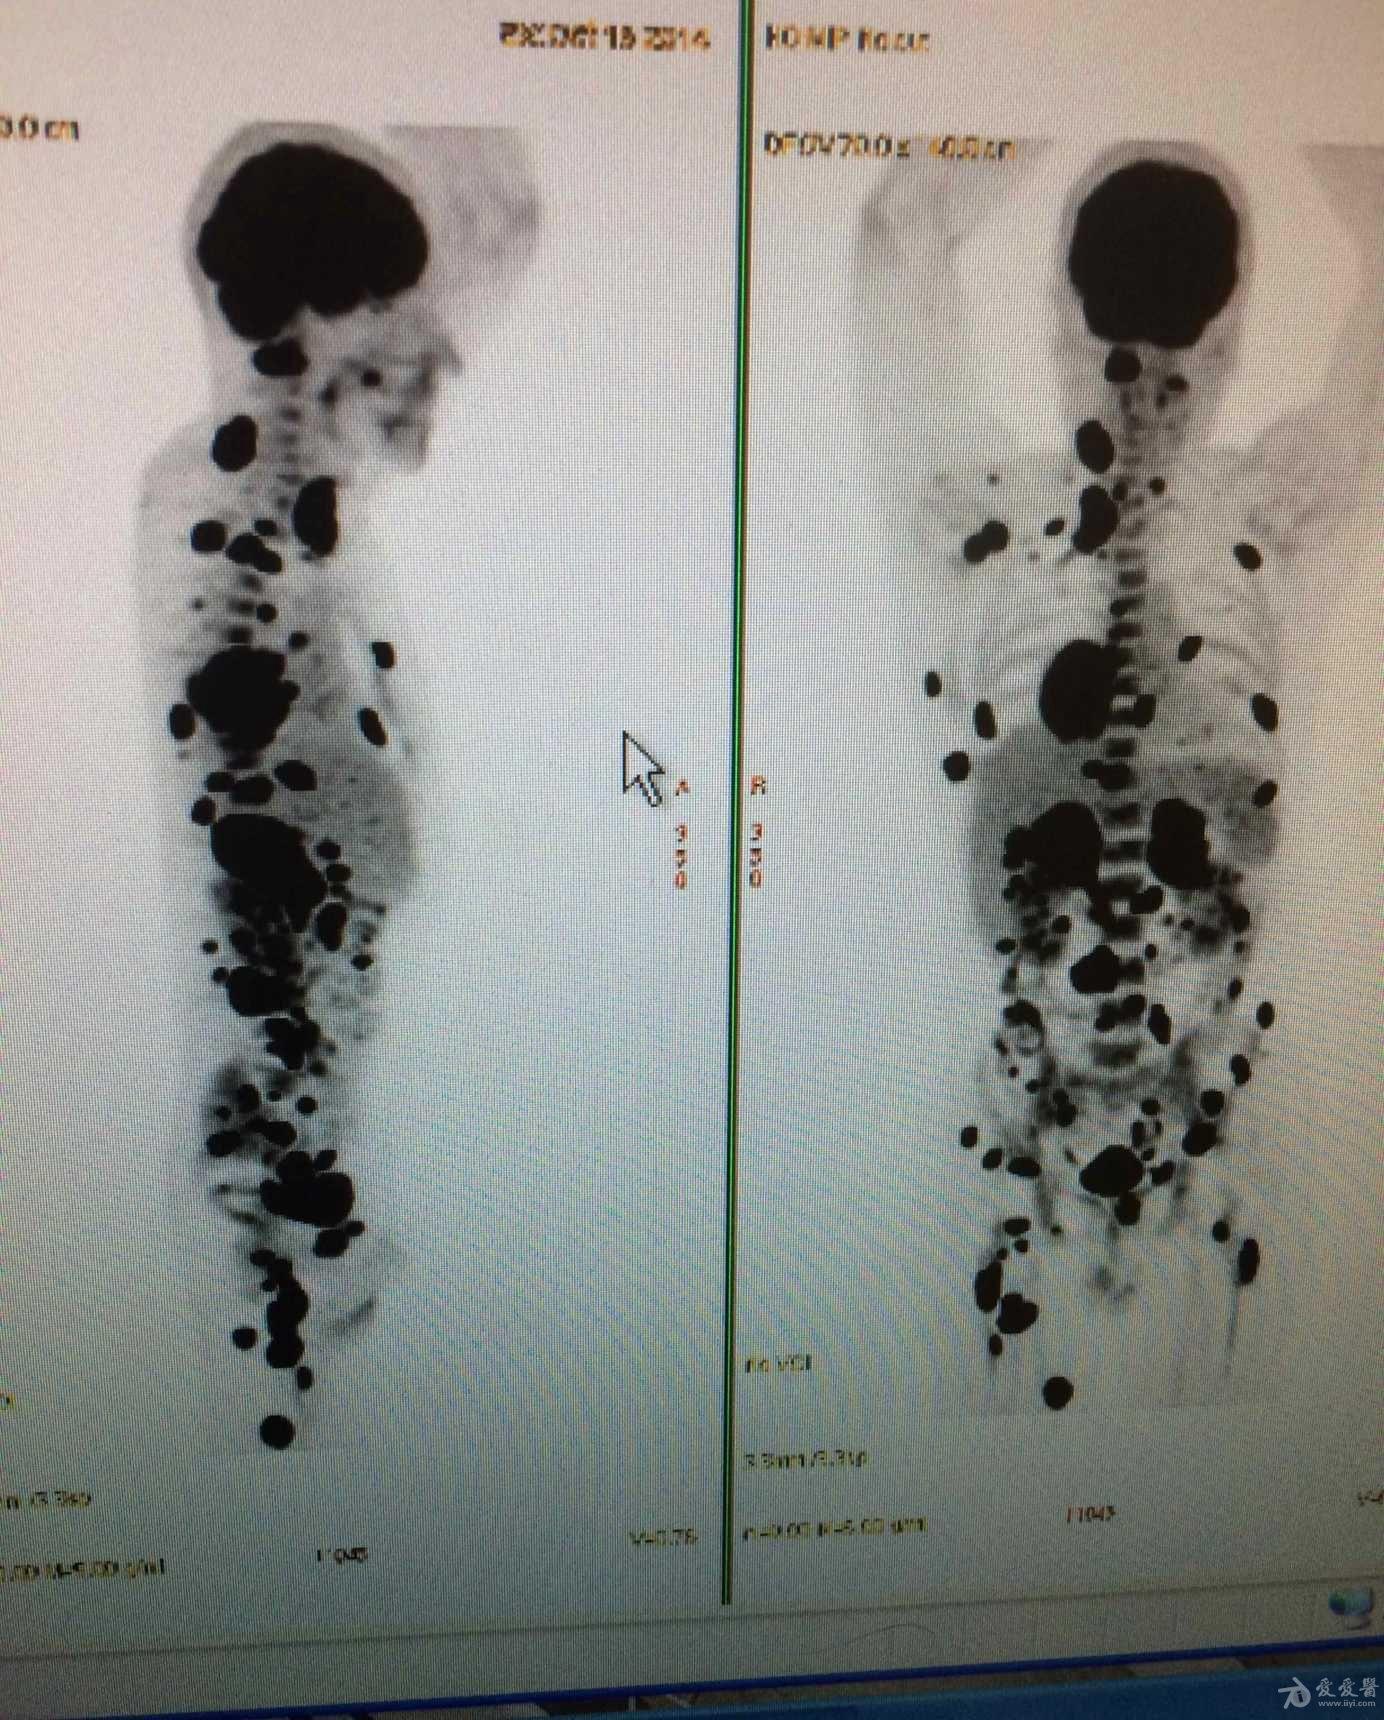

男,运动员,无病史,刚被诊断出肺癌,这是他的pet扫描图,这是全身都转移

图片尺寸1384x1720